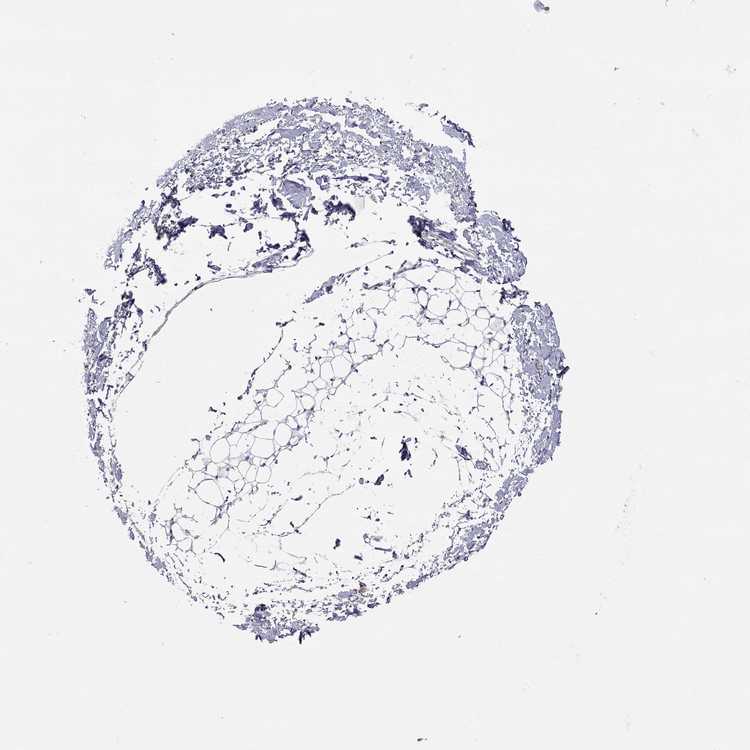

Female, age 52

Breast sample 373

nTPM: 0

Cell types%

Glandular cells:

15

Adipocytes:

5

Other cell types:

80